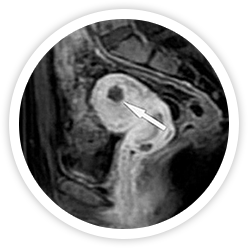

하이푸는 고강도 집속 초음파를 이용하여 입체적인 종양조직의 괴사를 유도하기 때문에 종양의 크기, 수, 모양, 위치에 따라

최적의 방법으로 종양조직의 괴사가 가능합니다. 괴사된 체내의 종양은 시간이 지나면 차차 없어집니다.

시술 전

시술 직후

시술 6개월 후

시술 1년 후